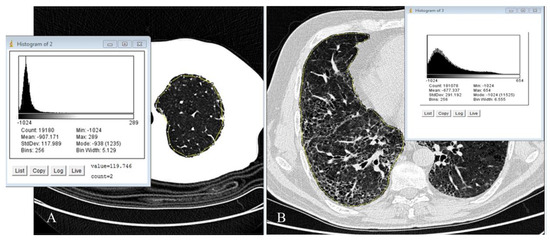

- Rea, G.; De Martino, M.; Capaccio, A.; Dolce, P.; Valente, T.; Castaldo, S. Comparative analysis of density histograms and visual scores in incremental and volumetric high-resolution computed tomography of the chest in idiopathic pulmonary fibrosis patients. Radiol. Med. 2021, 126, 599–607. [Google Scholar] [CrossRef]

- Ariani, A.; Carotti, M.; Gutierrez, M.; Bichisecchi, E.; Grassi, W.; Giuseppetti, G.M.; Salaffi, F. Utility of an open-source DICOM viewer software (OsiriX) to assess pulmonary fibrosis in systemic sclerosis: Preliminary results. Rheumatol. Int. 2014, 34, 511–516. [Google Scholar] [CrossRef] [PubMed]

- Sverzellati, N.; Zompatori, M.; De Luca, G.; Chetta, A.; Bnà, C.; Ormitti, F.; Cobelli, R. Evaluation of quantitative CT indexes in idiopathic interstitial pneumonitis using a low-dose technique. Eur. J. Radiol. 2005, 56, 370–375. [Google Scholar] [CrossRef] [PubMed]

- Ash, S.Y.; Harmouche, R.; Vallejo, D.L.; Villalba, J.A.; Ostridge, K.; Gunville, R.; Come, C.E.; Onieva Onieva, J.; Ross, J.C.; Hunninghake, G.M.; et al. Densitometric and local histogram-based analysis of computed tomography images in patients with idiopathic pulmonary fibrosis. Respir. Res. 2017, 18, 45. [Google Scholar] [CrossRef]